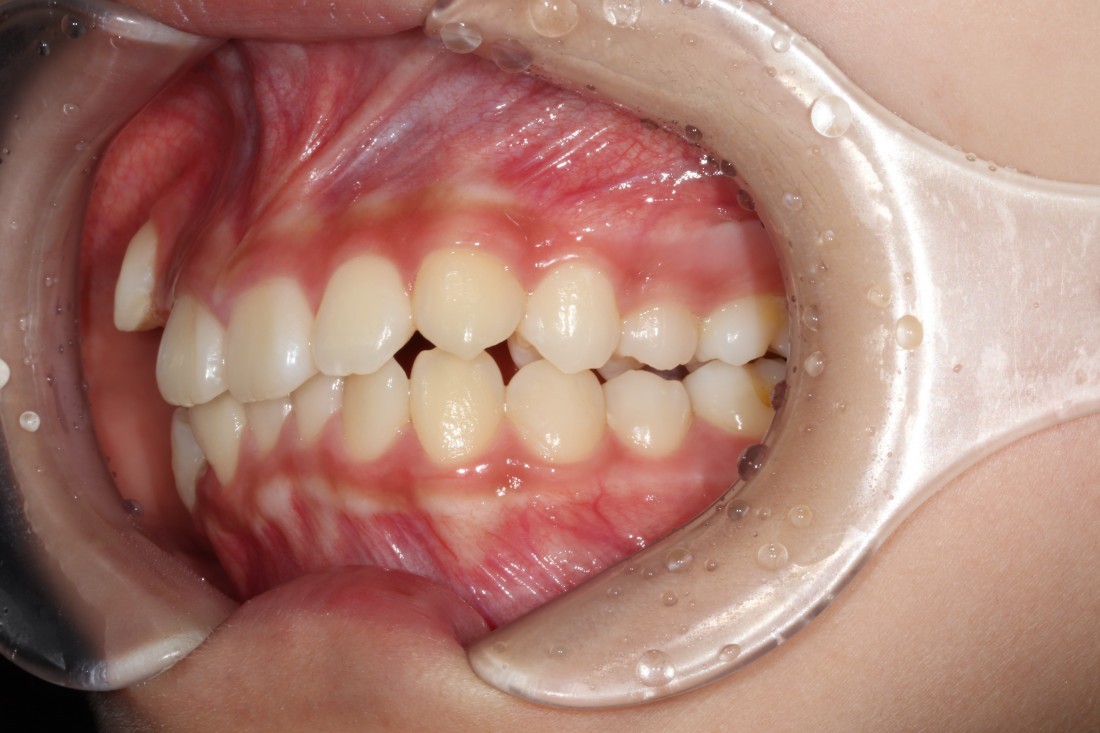

비발치교정만이 무조건 좋은 것이라고

생각하시는 분들이 있을 수 있지만,

발치교정이 필요한 경우에

비발치교정으로 교정하는 경우

치열이 가지런해져도 치아가 돌출되거나

치아 뿌리가 턱뼈 밖으로 밀려나가는 등

다양한 부작용 케이스가 있기 때문에

각 개인별로 최적의 치료계획을 세우는 것이

광주 발치교정 치과의

성공적인 발치교정 노하우입니다.